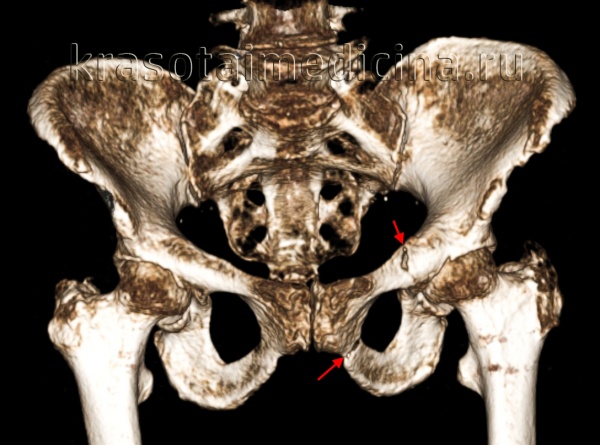

Для определения типа перелома, оценки степени смещения, решения вопроса о необходимости оперативного лечения и выбора соответствующего доступа необходимо провести рентгенологическое исследование таза в косых проекциях и КТ. Существуют разные хирургические доступы к вертлужной впадине. Среди них доступ по Kocher-Langenbeck, подвздошно-паховый доступ, расширенный подвздошно-бедренный, модифицированный подвздошно-бедренный, по Stoppa, трехлучевой доступ, комбинированный переднезадний и чрескожный доступы.

Для уточнения диагноза выполняют обзорную рентгенографию таза и рентгенографию поврежденного сустава в трех дополнительных проекциях. По возможности пациента направляют на КТ таза, поскольку эта методика позволяет более точно оценить тяжесть травмы и характер смещения отломков. Диагностическая ценность компьютерной томографии возрастает при повреждениях задней колонны и оскольчатых переломах.

Выбор доступа зависит от типа перелома и общего состояния пациента. Пространственное представление расположения костных фрагментов является неотъемлемой частью предоперационного планирования. Для предупреждения некроза кости необходимо бережно относиться к мягким тканям. Следует обеспечить защиту жизненноважных нервов и сосудов. Костные фрагменты должны быть с максимальной точностью сопоставлены и стабильно фиксированы, как правило, шурупами и пластинами, которые не должны соприкасаться с суставной поверхностью. Возможность проведения операций под контролем усилителя рентгеновского изображения (ЭОП) позволяет правильно расположить ортопедические металлоконструкции в области вертлужной впадины. По мере накопления опыта оперативного лечения происходит снижение частоты осложнений и неудовлетворительных результатов.